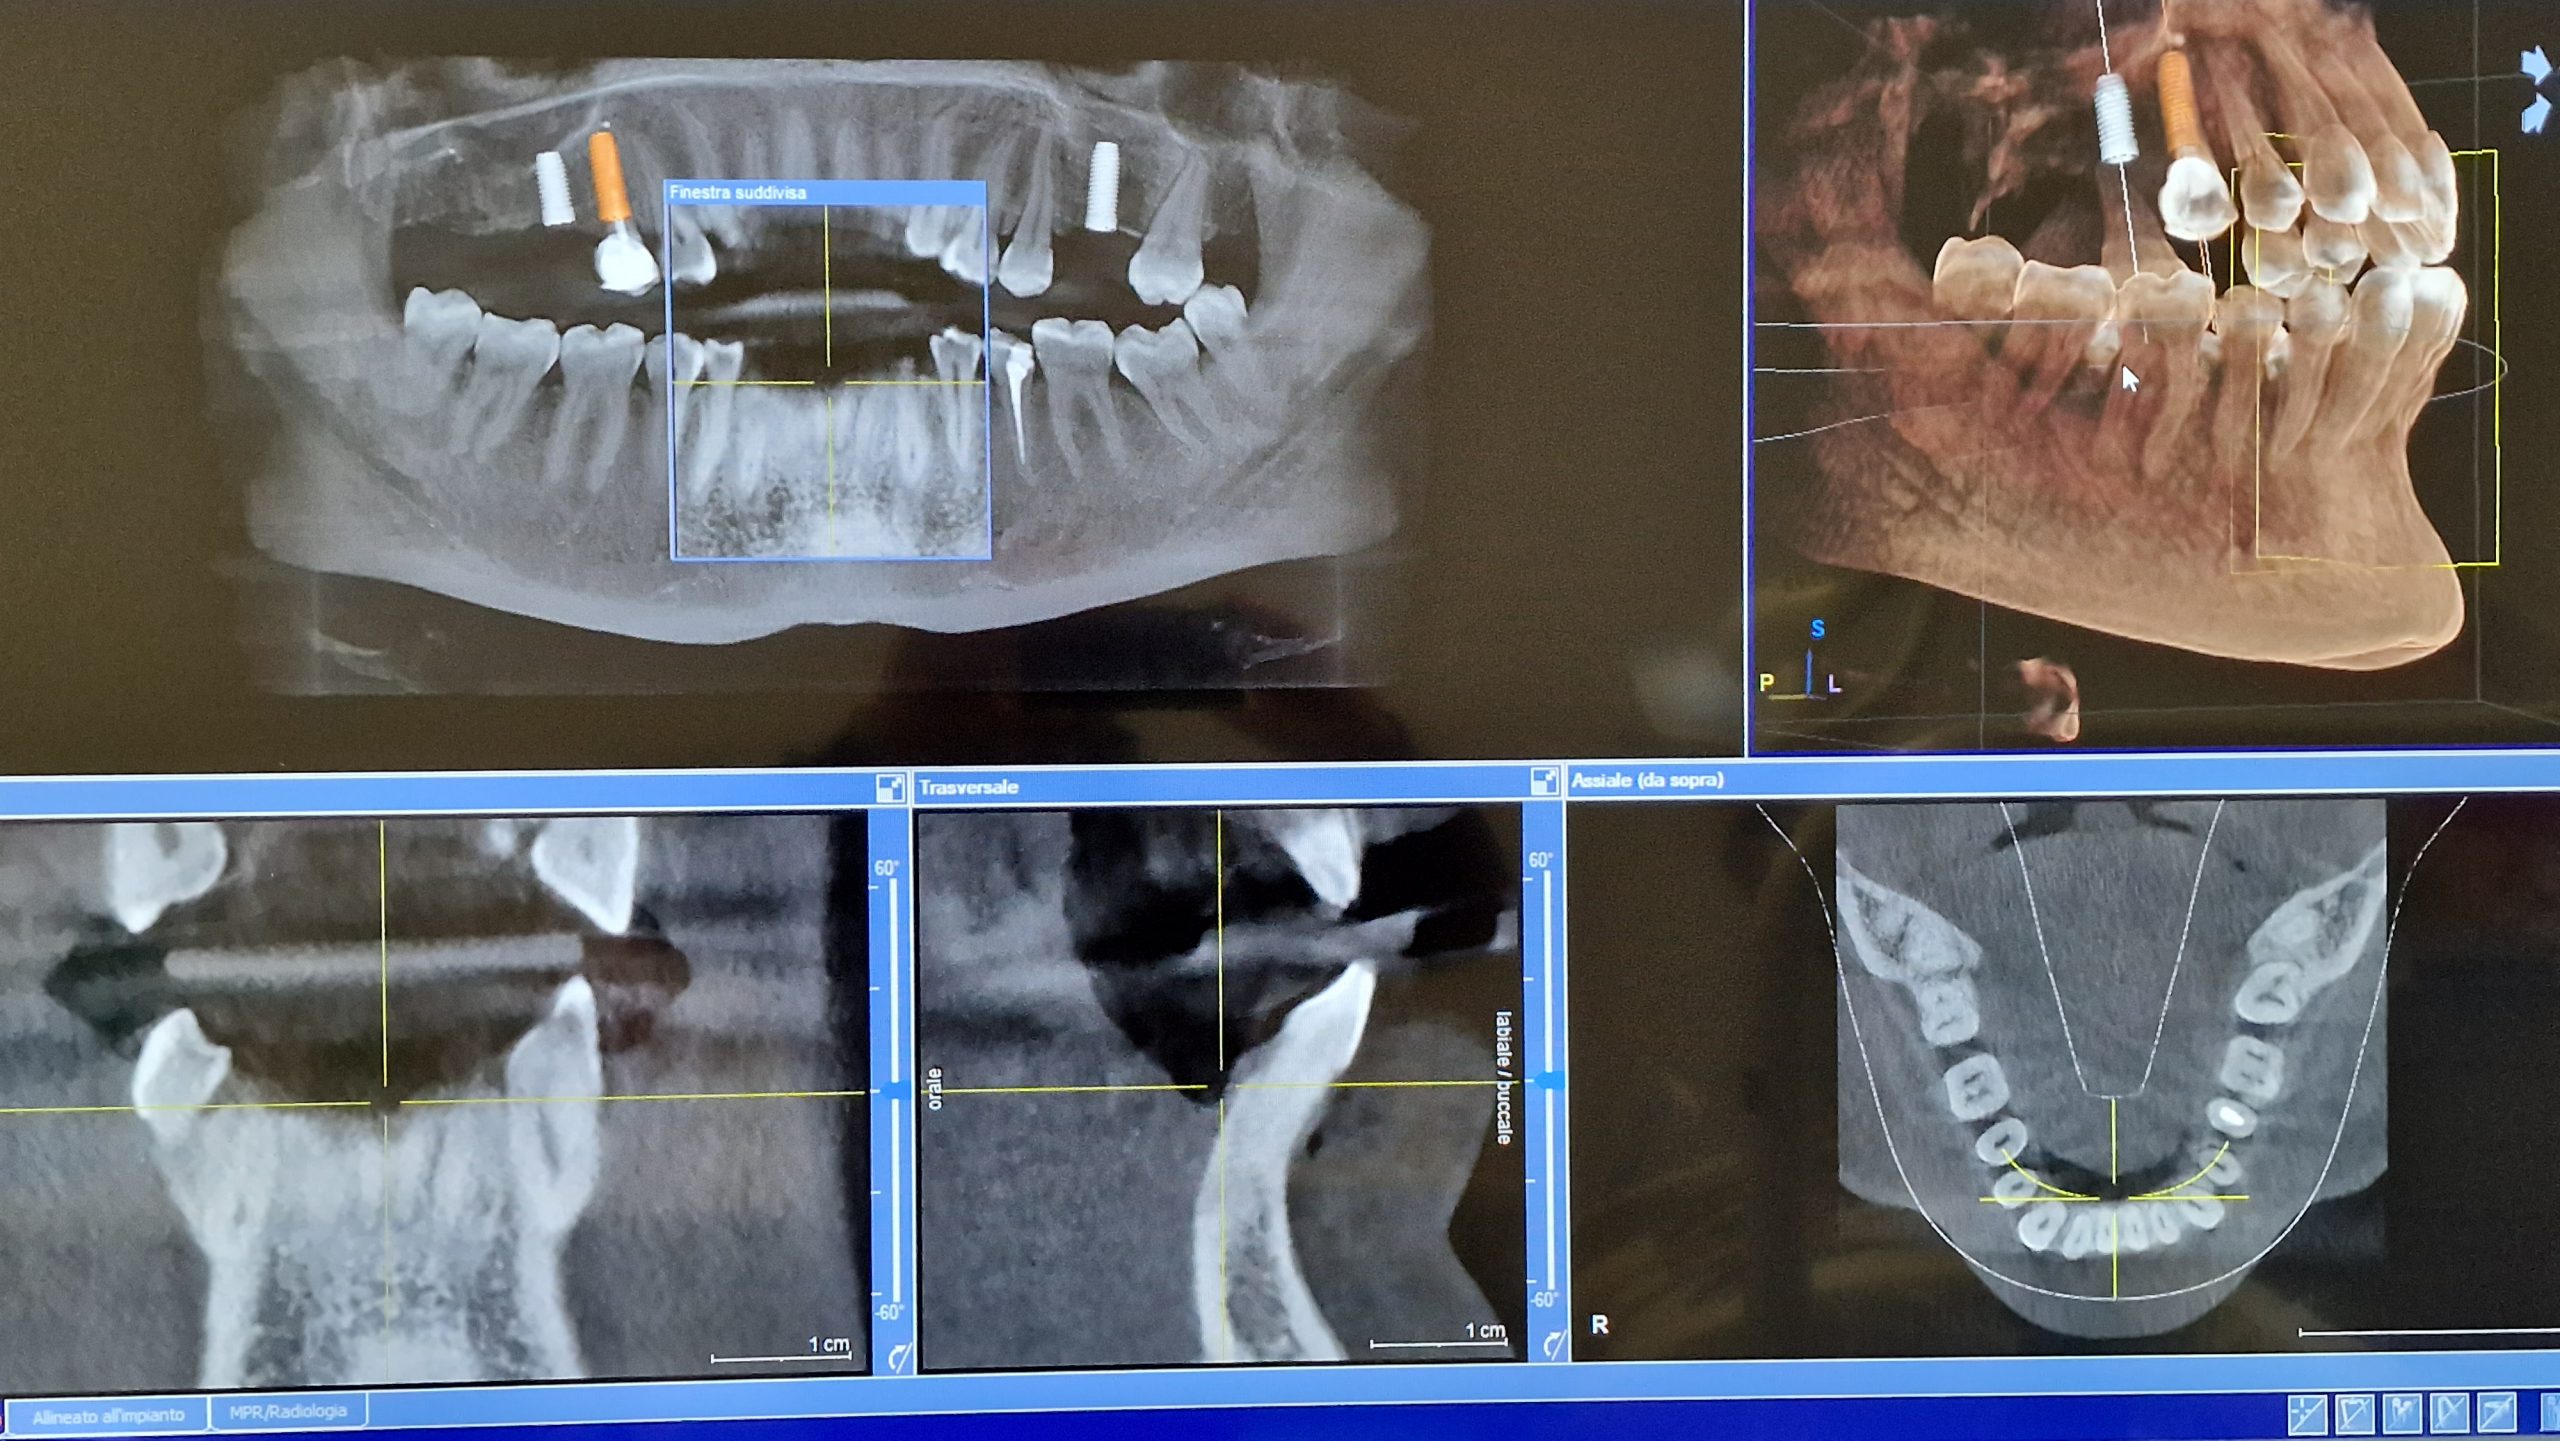

CBTC

Conosciuta come dentascan è un esame di 2° livello che serve per avere un esame volumetrico delle ossa mascellari per poter pianificare una chirurgia avanzata (impianti, denti del giudizio, chirurgia rigenerativa)